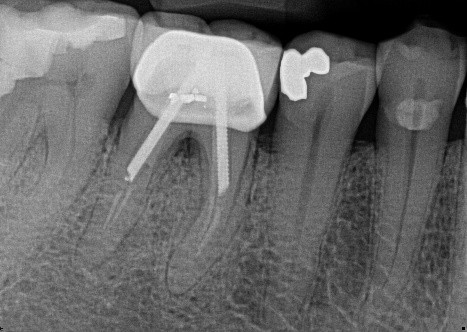

14. (Select ONE OR MORE correct answer)

Which of the following is true regarding dental implant at site 3.6?